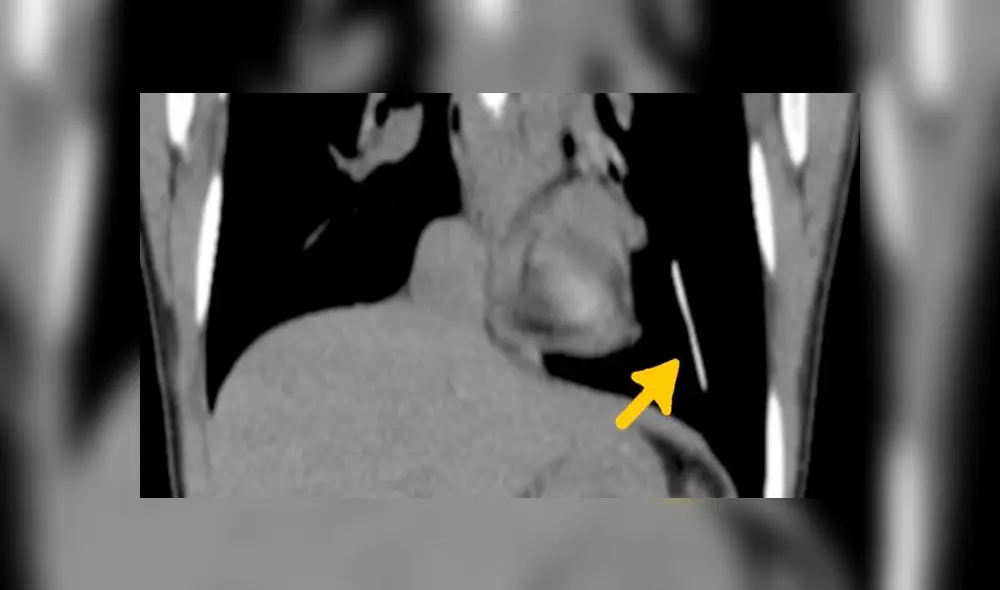

Al no poder ubicar el implante en el área del bíceps ni en los alrededores, los médicos realizaron un ultrasonido. Lo que hallaron desconcertó a todos en la sala.

El implante se había alojado en el pulmón izquierdo. En ese momento, no podían entender cómo había migrado desde una zona muscular (su brazo) hasta el interior de su órgano respiratorio.

Los médicos hicieron una cirugía asistida por video para localizar el implante. Luego, hicieron una intervención quirúrgica en el área del pecho para extraer el objeto.